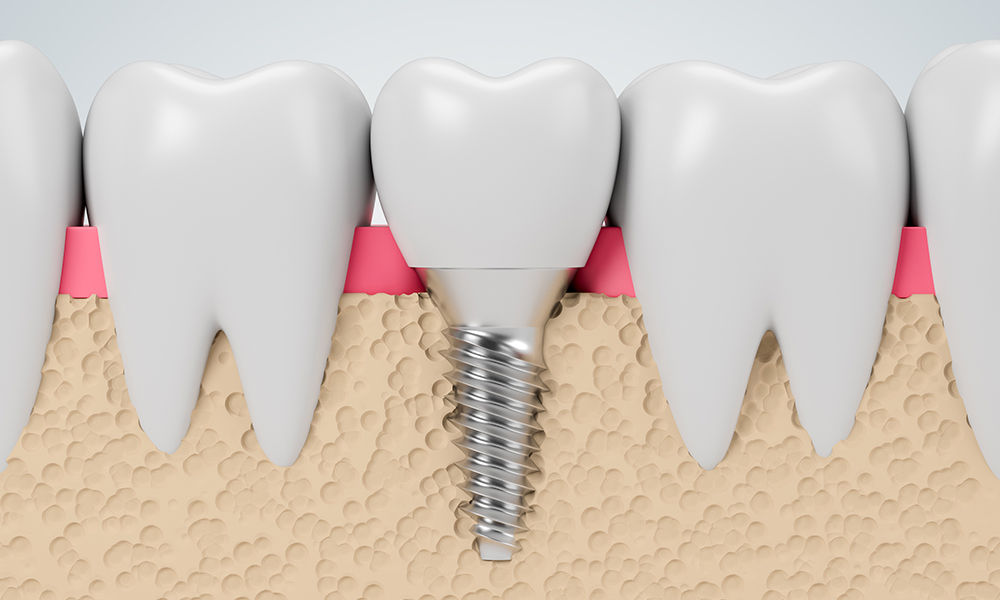

Los implantes son raíces artificiales de titano que se fijan en el hueso y sobre ellas colocamos las coronas que sustituyen los dientes perdidos. Es la mejor alternativa terapéutica para devolver la estética y función de un diente. Existen numerosos tipos de tratamientos dentro de esta especialidad:

Los implantes son la mejor alternativa terapéutica para devolver la estética y función de un diente.